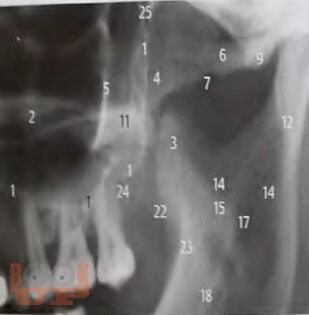

Алгоритм лучевой диагностики при синдроме болевой дисфункции височно-нижнечелюстного сустава

В учебно-методическом пособии представлен доступный алгоритм лучевой диагностики при синдроме болевой дисфункции височно-нижнечелюстного сустава. Алгоритм дает возможность повысить точность диагностики, а следовательно, и эффективность лечения пациентов, индивидуализировать методы терапии каждого больного.

Пособие предназначено для врачей разных специальностей: стоматологов, неврологов и рентгенологов, а также интернов и ординаторов.